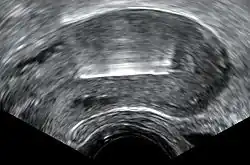

Transvaginal ultrasonography showing a perforated copper IUD as a hyperechoic (rendered as bright) line at right, 3 centimeters away from the uterus at left. The IUD is surrounded by a hypoechoic (dark) foreign-body granuloma.

Perforation of the device through the uterine wall typically occurs at the time of placement, though it may occur spontaneously during the period of use. Estimates of the rate of perforation vary from 1.1 per 1000 to 1 per 3000 copper IUD insertions.[1][11] Perforation may be slightly more common in people using the copper IUD while breastfeeding.[28]

Due to its inflammatory mechanism of action, a copper IUD that has completely perforated typically requires surgical removal due to the formation of dense adhesions around the device. A device embedded in the uterine wall may be removed hysteroscopically or surgically.[1][16]